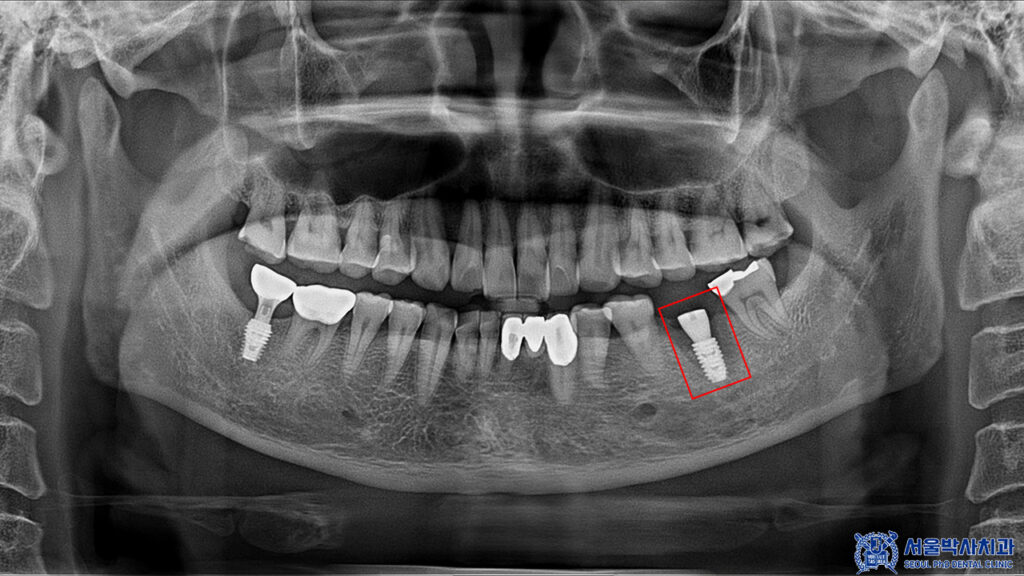

이후 임플란트의 치유기간을 거치고

뼈와의 결합이 안정적으로

이루어진 것을 확인 후

뒤 치아와 함께 보철 작업을

시작하였습니다.

본원 원내기공소에서 상주하는

10년 차 이상의 전문 치과기공실장님이

정교하게 제작한 개인맞춤형

보철물을 세팅해 드렸습니다.

마무리 후 사진입니다.

환자분께서는 원래 다니던 치과에서

보철치료를 받았던 부위가 아프셨는데

본원에서 임플란트 1개를 받아보시고

매우 만족해주셨습니다.